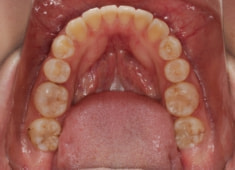

治療後(1年12ヶ月後)